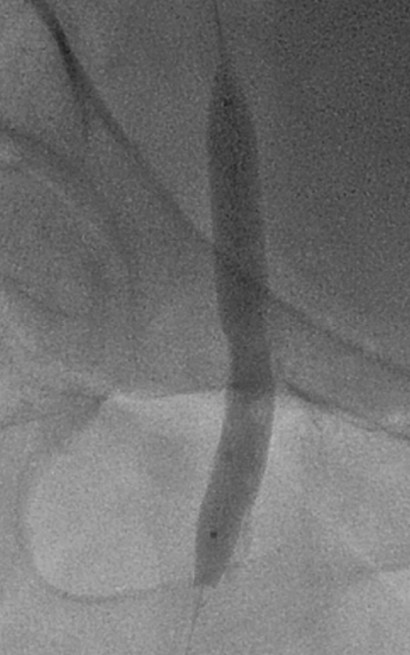

Left femoral artery accessed under ultrasound guidance. Coronary angiography showed patent LM and LAD, mild distal LCx and OM stenosis, and irregular RCA lumen. Right lower limb angiography revealed a stumpless chronic total occlusion at the superficial femoral artery ostium with collaterals from the profunda femoris. Distal runoff was maintained through patent popliteal and anterior tibial arteries.

An antegrade approach was first attempted via left femoral access using an 8 Fr long sheath advanced to the right femoral artery. Despite multiple manipulations, the wire and microcatheter failed to cross the calcified lesion at the superficial femoral artery ostium. The wire could engage the plaque but was unable to advance through the dense calcium. A retrograde approach was then established by puncturing the proximal superficial femoral artery under ultrasound guidance. The connection between the retrograde and antegrade wires was confirmed under orthogonal fluoroscopy. Using a rendezvous technique, the retrograde wire was advanced into the antegrade guiding catheter and externalized through the contralateral sheath, creating a continuous guidewire pathway.After wire externalization, sequential intraplaque and extraplaque rotational atherectomy were performed to modify both deep and superficial calcium. This ablation provided effective vessel preparation using a small burr size, improving compliance while minimizing procedural risk. Intravascular lithotripsy was subsequently performed to further optimize vessel expansion.Final high-pressure dilation achieved full luminal gain, followed by drug-coated balloon angioplasty as the definitive therapy. The final angiogram demonstrated excellent vessel expansion, preserved bifurcation flow, and no evidence of dissection, perforation.

This case demonstrates the feasibility of combining dual-plane rotational atherectomy and intravascular lithotripsy to treat a heavily calcified superficial femoral artery ostial occlusion. The rendezvous technique enabled successful wire passage when the antegrade approach failed, allowing complete lesion modification and optimal luminal expansion without complications. This hybrid strategy provides an effective option for complex, calcified femoral bifurcation disease.